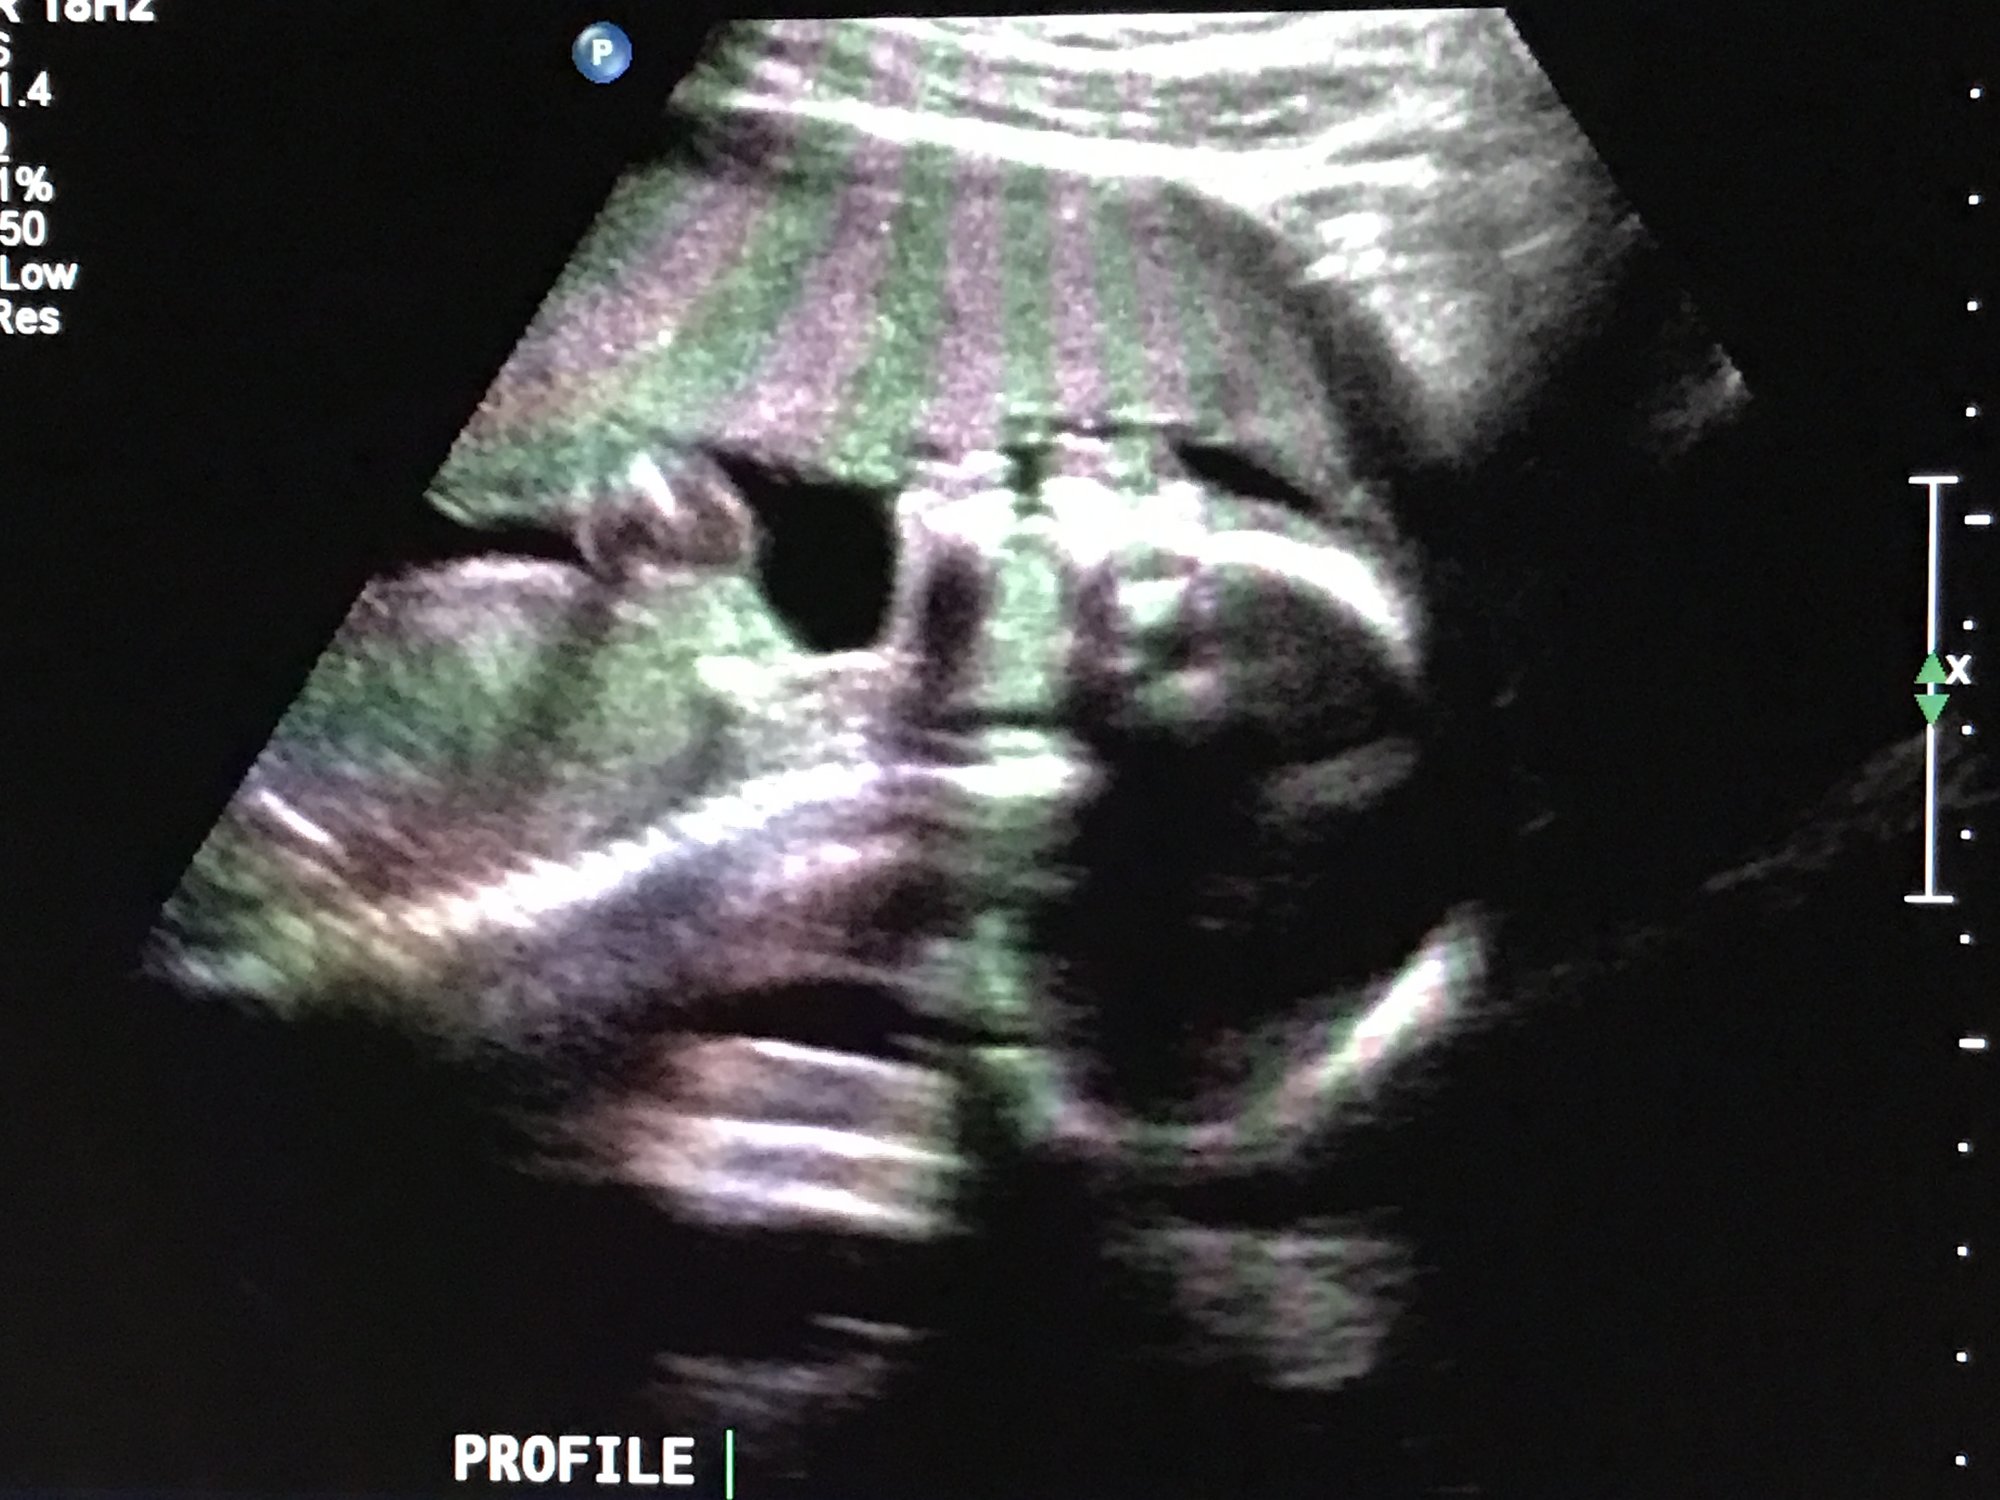

The doctor surprised me with an anatomy scan this morning! I'm 19w, scheduled to see a specialist next month for a fetal echocardiogram (just because we did IVF, and apparently that's standard.) This morning, regular OB was like "Eh, you're here and you haven't seen him in a while. Want to do the anatomy scan today?" I would have liked my husband to be there...but not enough to turn down an ultrasound!

Our little nerd stared down the "camera" the whole time. Would have loved one of those adorable profile shots...instead, he looks a little...ghoulish ;-) At least his little feet are cute!